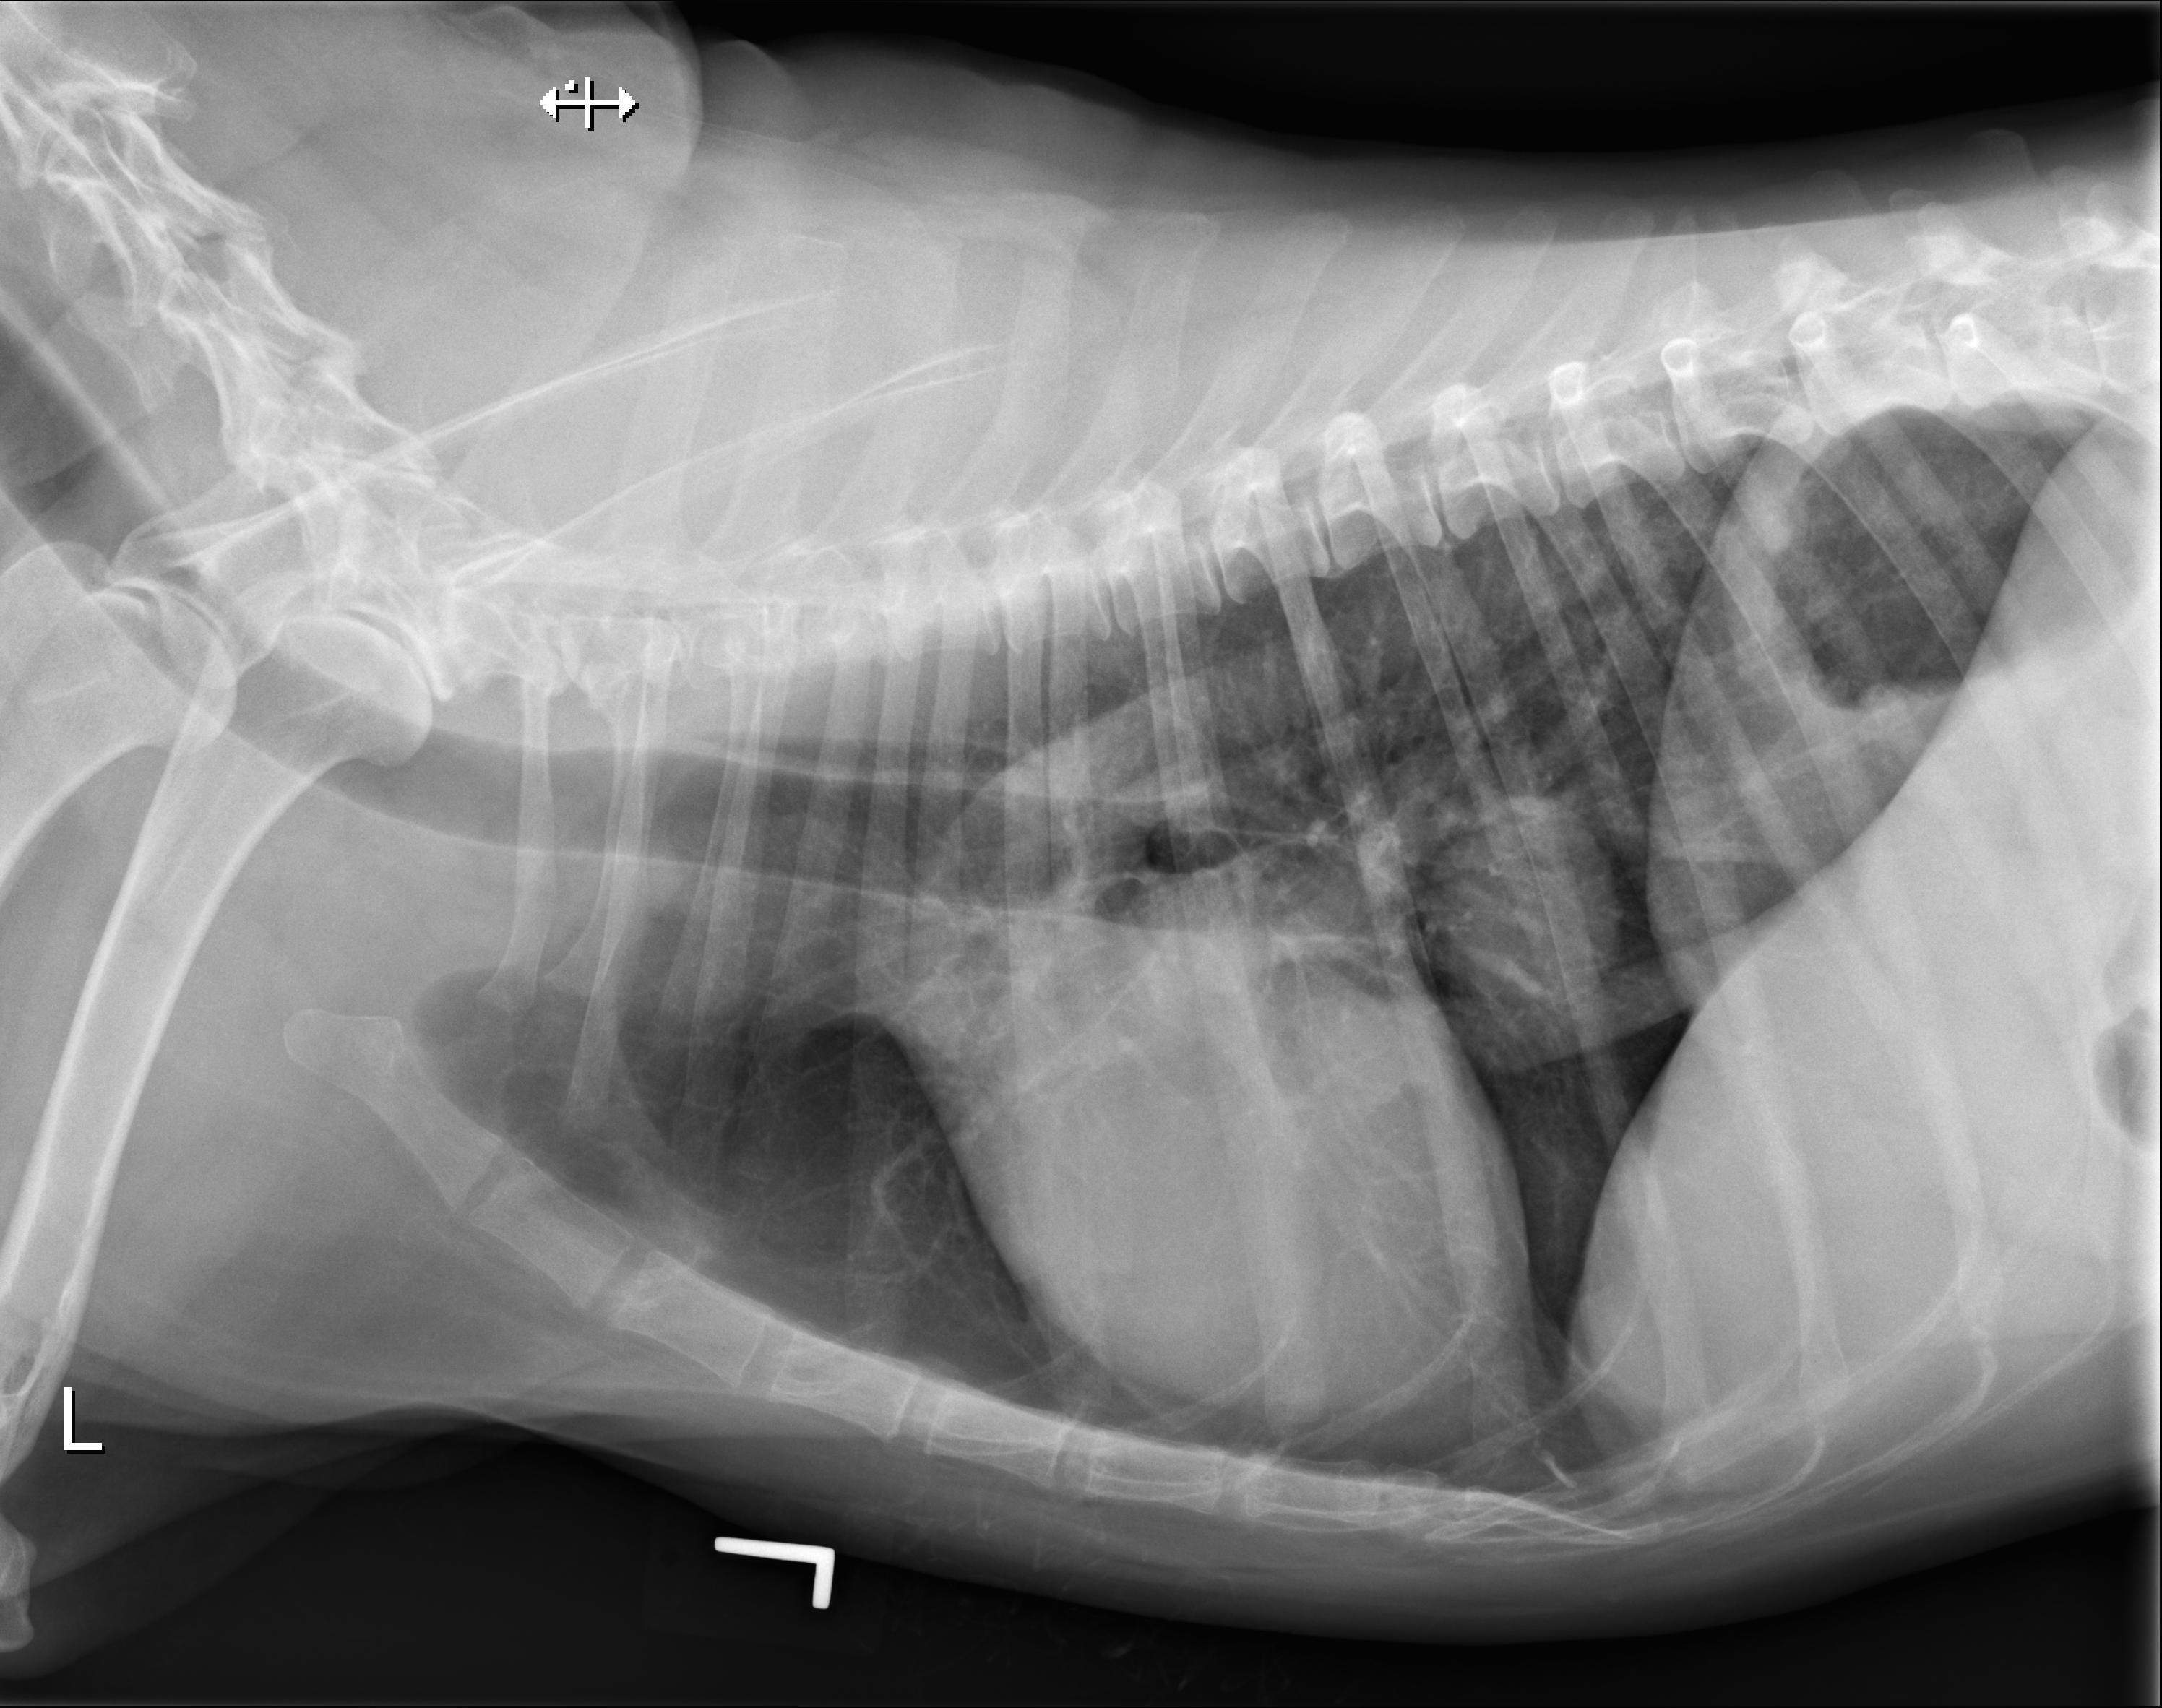

一只慢性肠病的犬

翻译:祁海丽;校对:石慧13 You have diagnosed an adult dog with a chronic enteropathy based ...

兽医英语学习中心翻译:祁海丽;校对:石慧13 You have diagnosed an adult dog with a chronic enteropathy based ...